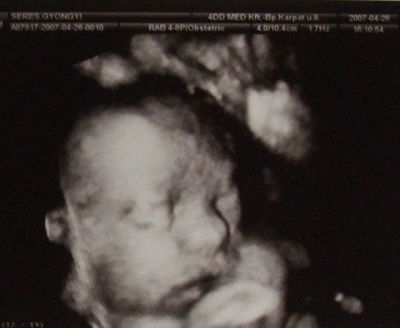

Kép Kép Kép

Ő a mi kisfiunk,itt 28 hetesek voltunk!

PÓCI AZ UTOLSÓ KÉPEN AZT LÁTOM AMIT GONDOLOK? :-)